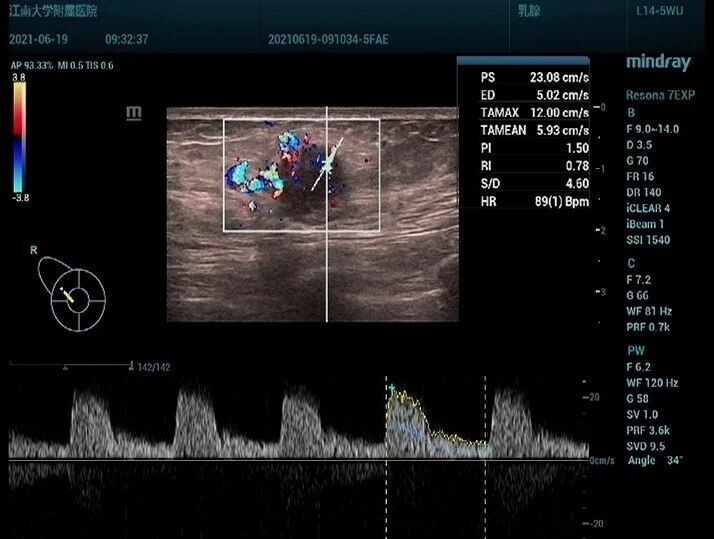

患者,女,63 岁,因右乳肿块一周入院,超声于右侧乳腺 10 点钟方向见一低回声结节,不规则形,边缘模糊(图 1),内部回声不均, CDFI 见较丰富血流信号(图 2), PW 测及高阻动脉血流频谱, RI:0.78 (图 3)。

图 2 CDFI 见较丰富血流信号

图 3 PW 测及高阻动脉血流频谱, RI:0.78